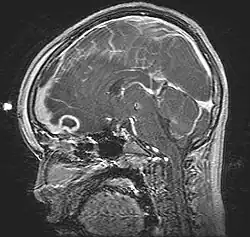

Pott's puffy tumor, spreading towards person's brain. MRI, T1, sagittal, gadolinium contrast. | |

Pott's puffy tumor, first described by Sir Percivall Pott in 1760, is a rare clinical entity characterized by subperiosteal abscess associated with osteomyelitis. It is characterized by an osteomyelitis of the frontal bone, either direct or through haematogenic spread. This results in a swelling on the forehead, hence the name. The infection can also spread inwards, leading to an intracranial abscess. Pott's puffy tumor can be associated with cortical vein thrombosis, epidural abscess, subdural empyema, and brain abscess.

Although it can affect all ages, it is mostly found among teenagers and adolescents. It is usually seen as a complication of frontal sinusitis or trauma. Medical imaging can be of use in the diagnosis and evaluation of the underlying cause and extent of the condition. Ultrasound is able to identify frontal bone osteomyelitis,[1] while computed tomography (CT) can evaluate bony erosion, and along with magnetic resonance imaging (MRI), can better appreciate the underlying cause and extent of possible intra-cranial extension/involvement.[2][3]